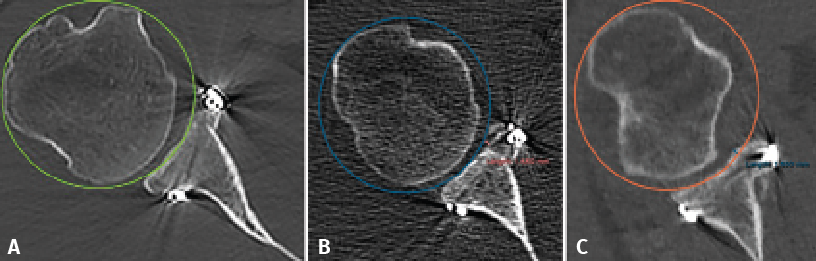

Figure 2. Evaluation of graft positioning in the sagittal section. Two lines are traced of a length equivalent to the size of the glenoid bone defect (B) and to the length of the graft covering the defect (A). Image A shows how most of the bone defect is covered by the graft - the latter therefore being considered to be well positioned. Image B shows that less than 90% of the bone defect is covered by the graft - the latter therefore being considered to be inadequately positioned.

Taking the posteroinferior glenoid border as reference, we traced a first circumference over its contour, and a second circumference above the previous one and tangential to the glenoid borders. The line joining the centre of both circumferences was taken to represent the axis of the glenoid cavity. Over this we estimated the point corresponding to the half and 25% of the glenoid height (Figure 1). The sagittal section was used to determine the position of the graft in the craniocaudal direction (Figure 2). The length (in mm) of the bone defect was measured (B), along with the amount of bone graft covering the defect (A). Percentage covering of the bone defect was estimated from the ratio between A and B. The graft was considered to be well positioned when the percentage coverage of the defect was at least 90%.